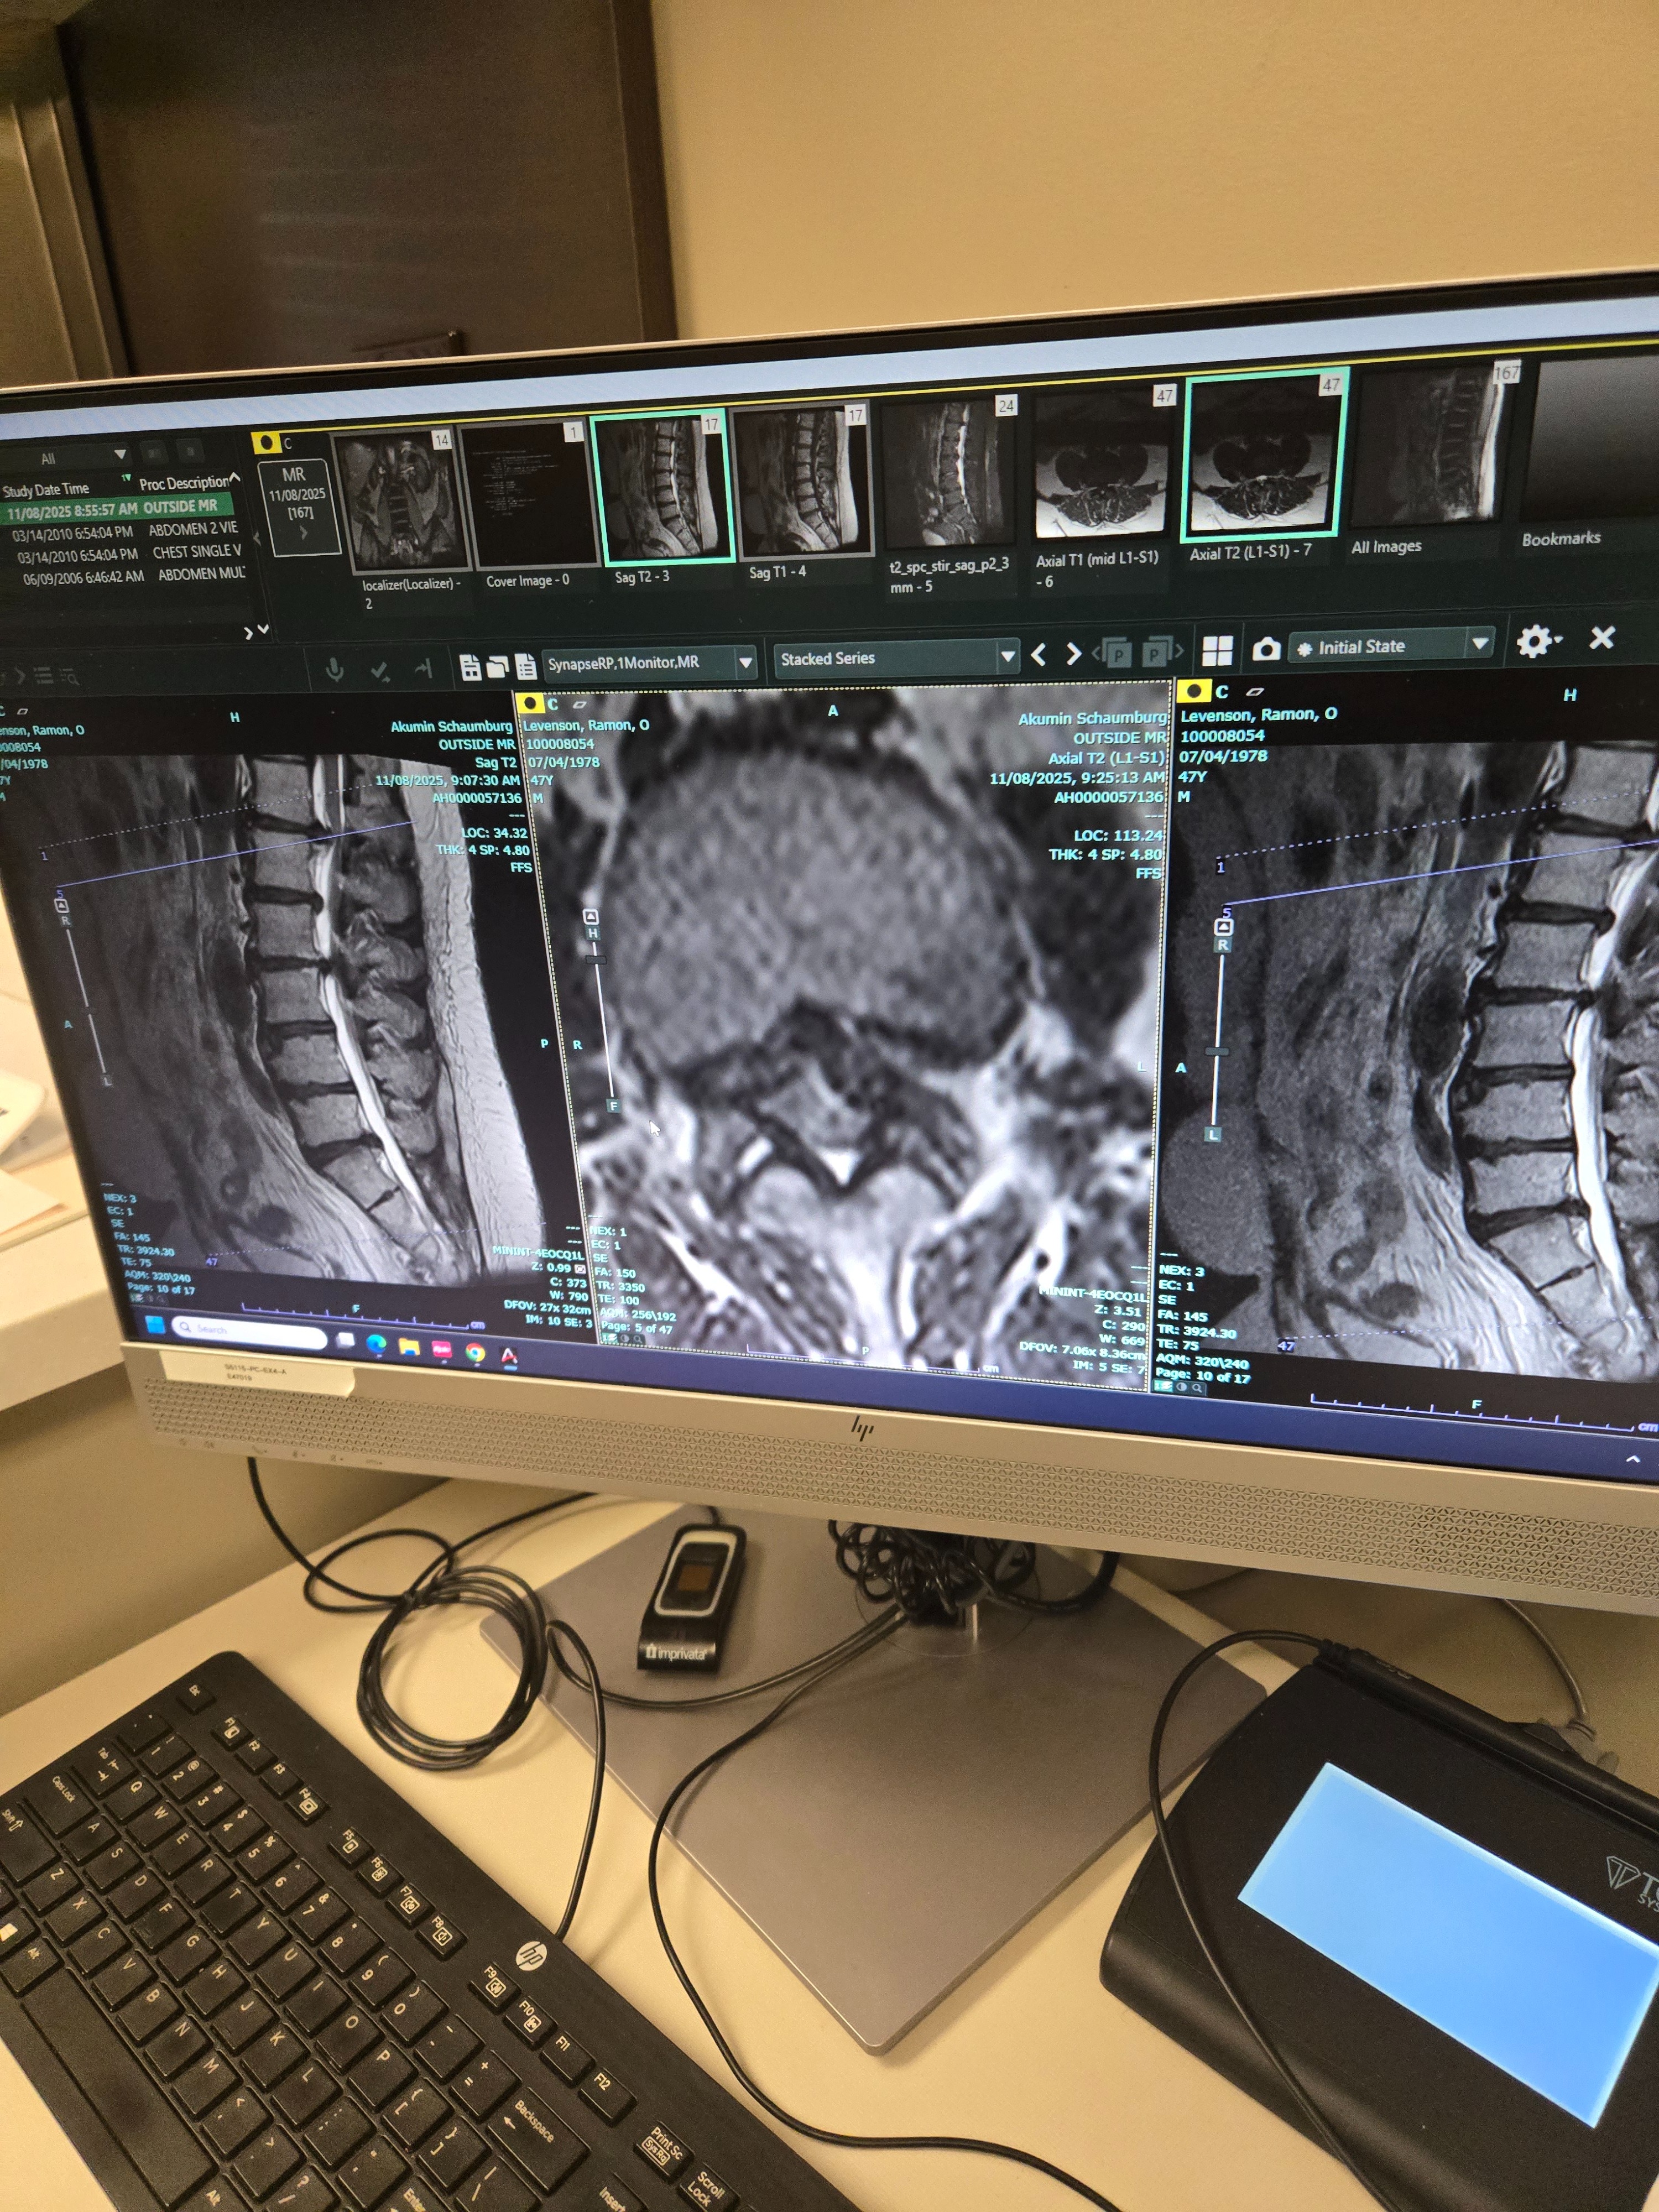

I recently had spinal surgery to deal with severe nerve pain that had been affecting my day-to-day life. During the surgery, there were unexpected complications- spinal tear and fluid leakage- that kept me in the hospital longer than planned and left me facing a much longer recovery and medical costs than I was prepared for.